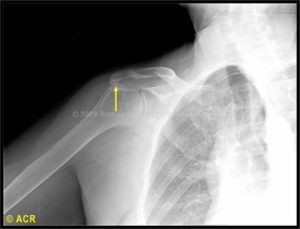

When you raise your arm to Shoulder height, the space between the acromion and rotator cuff narrows. The acromion can rub against (or "impinge" on) the tendon and the bursa, causing irritation and pain.

Arthroscopic Subacromial Decompresion is a procedure in which surgical instruments are inserted into two or three small puncture wounds around your Shoulder. Your doctor examines your Shoulder through a fiberoptic scope connected to a television camera. He or she guides the small instruments using a video monitor, and removes bone and soft tissue. In most cases, the front edge of the Acromion is removed along with some of the bursal tissue.